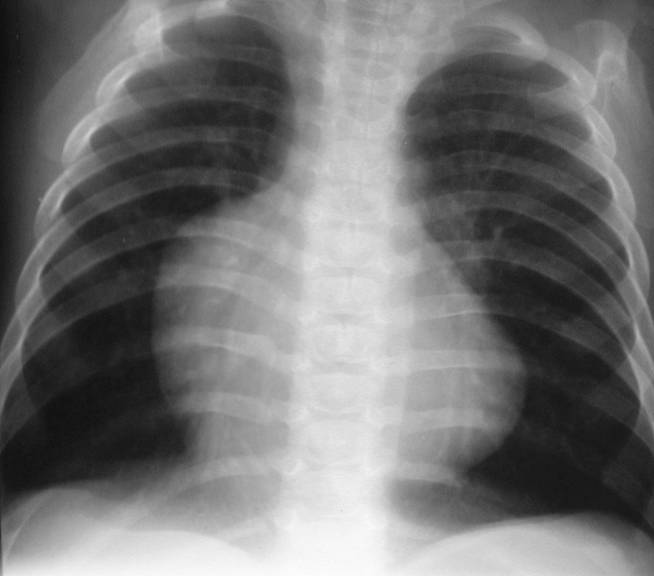

Decreased Flow

Small hila

Fewer than

normal blood

vessels